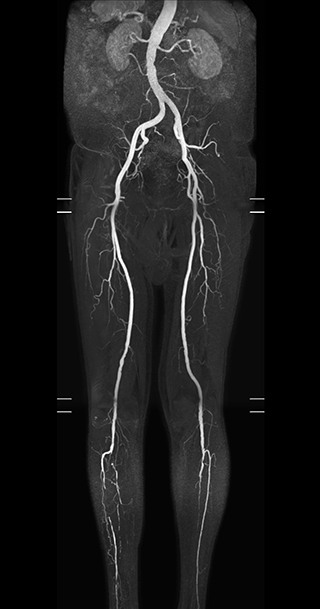

“In our peripheral MRA run-off studies with Ambition we realize key benefits, including outstanding image quality and significantly reduced breath-hold and scan times, which not only benefit the patient, but also provide the opportunity to add sequences that could aid in diagnosis,” Dr. Peña says.

“Before we had Ingenia Ambition, our CE-MRA run-off studies would first acquire a dynamic pre-contrast scan with 20-25-second breath-holds, then inject the contrast, do another acquisition and then subtract the two,” says Avila. “Now, mDIXON XD allows us to complete the study in just one single pass – without need for a pre-exam – which eliminates subtraction artifacts and almost halves the scan time. In addition, mDIXON provides much better background suppression, which really improves vesselto-background contrast. And, thanks to Compressed SENSE, the single breath-hold is not long and we improve image resolution.”

The subtractionless peripheral MR angiography shows improved vessel-to-background contrast and high resolution. Ingenia Ambition 1.5T.

The time saved by Compressed SENSE and mDIXON XD is sometimes used to include additional sequences. An example are peripheral MRA studies, in which Compressed SENSE and mDIXON XD help achieve a 5- to 10-minute reduction in scanning time. This brings the total time down, from the 45 minutes needed with their previous system to about 30 to 35 minutes on Ingenia Ambition, thus providing ample time to include additional sequences.

“These scans are so fast now that we have been able to add a non-contrast MRA sequence within the same timeslot. We compare the respective image quality with the goal to determine whether the non-contrast sequence could be an alternative for patients who can’t tolerate gadolinium contrast agents due to poor kidney function,” says Avila. “We find the image quality of the non-contrast sequence so good that we can now also offer peripheral MRA to these patients whom we had been unable to serve before Ambition, so that has been great.”

Performed on Ingenia Ambition. FOV 430 mm, voxels 1.3 x 1.3 x3.0 mm, 130 slices, Breath hold 16.6 sec